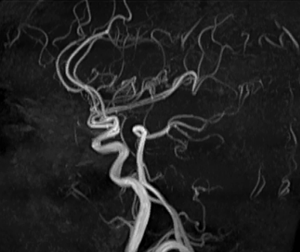

頭部MRA画像

頭部MRA画像

MRIとは、磁気共鳴画像診断装置(Magnetic Resonance Imaging)の略で、人体の中にたくさん存在している水の状態を、非常に強い磁石の力を用いて信号とし、コンピュータで処理して画像にする検査です。また、放射線を使用せずに検査を行うため被ばくがなく、造影剤を使用せずに血管を描出することが可能です。検査時間は約20 ~ 30分、造影剤を使用する検査では1時間程度かかることがあります。当センターでは3.0T装置と1.5T装置が導入されており、高分解能3D画像や非造影血管撮影などが可能です。このたび、2024年に1.5T装置のバージョンアップを行い、今までより短時間かつ高精度に検査を行えるようになりました。

頭部⾎管

頭部⾎管